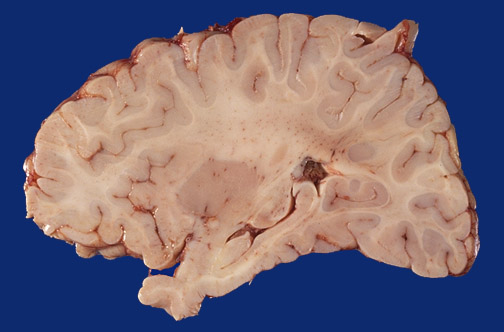

A normal term infant brain is shown in sagittal section lateral to the midline. Identify the following regions in the image above: Hippocampus - Putamen